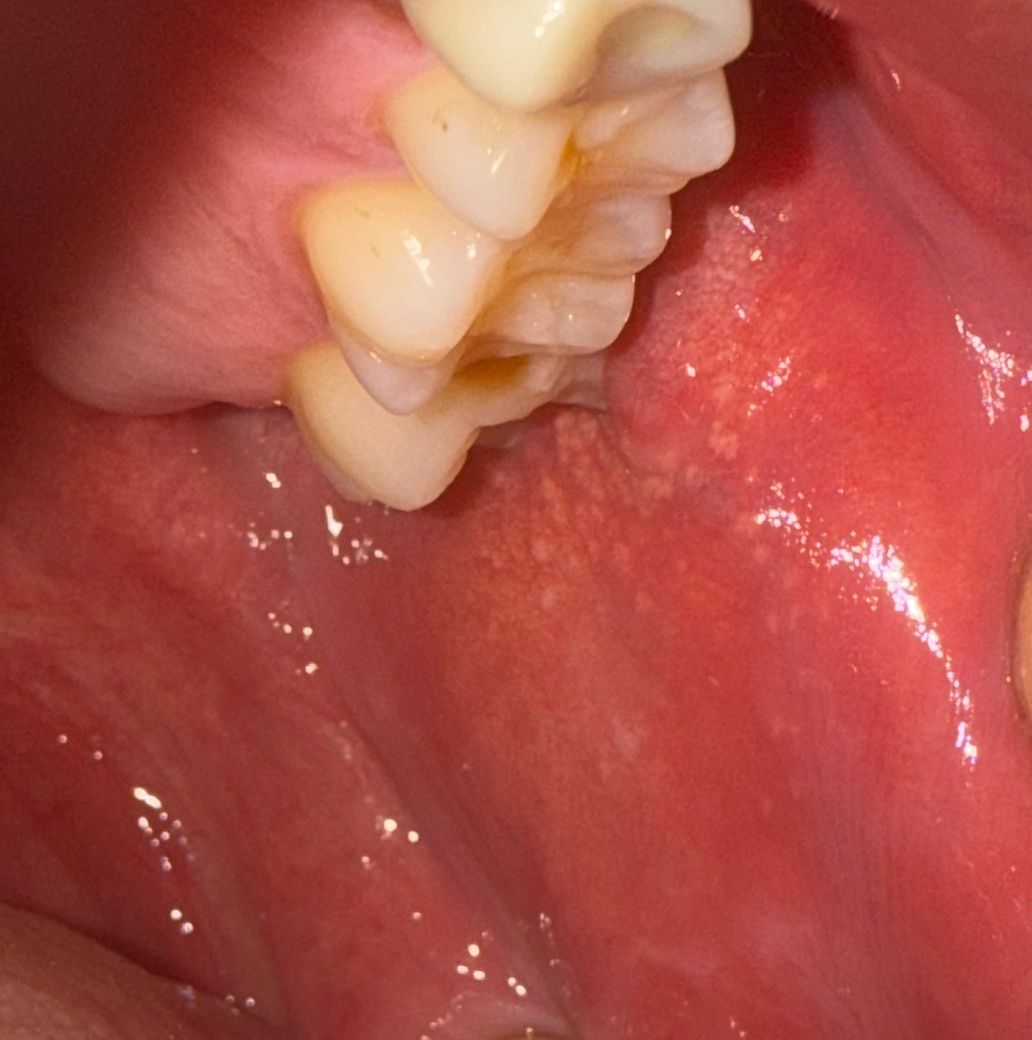

입안에 혹? 멍울? 하얀 반점이 있는데 뭘까요??

입안에 볼 쪽에 혹? 멍울?이 있고 하얀 반점이 있습니다. 어금니쪽 뭘까요? 구강암인가요? 반대편에는 혹은 없고 저렇게 자그마한 점? 비슷한건 있습니다. 생긴지는 한달정도 됐습니다.

• 1번 째 사진

일반적으로 하얀 반점이나 혹이 입안에 생겼을 때, 바로 구강암으로 의심할 필요는 없습니다. 구강 내에서 흔히 발생할 수 있는 문제로는 구내염, 물집, 피지선 낭종, 혐기성 염증 등이 있을 수 있어요. 하얀 반점은 백반증이나 백선(oral thrush)과 같은 감염으로 나타날 수 있는데, 이는 곰팡이 감염이나 바이러스 감염과 관련이 있을 수 있죠

입안의 혹이나 멍울은 때때로 타박상이나 침샘의 감염, 양성 종양(피지선 낭종)으로 인해 생길 수도 있습니다. 만약 한 달 이상 지속되고 크기가 커진다면, 이비인후과나 치과 진료 보시는게 중요 해 보여요

구강암은 일반적으로 오래 지속되는 통증이나 상처와 함께 발생하며, 하얀 반점이나 혹만으로 진단할 수는 없습니다. 이를 확인하기 위해서는 구강내 검진 및 필요시 조직 검사(생검) 등의 추가 진단이 필요할 수 있습니다.